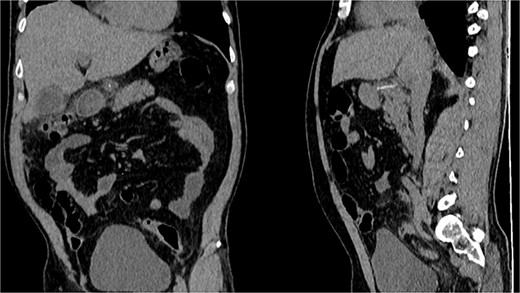

CT, the location of the fishbone in the lesser sac embedded in the pancreas.

With these findings, surgical consultation was required, and surgery was decided. On laparotomy, multiple adhesions were seen between the transverse colon and stomach. After opening the lesser sac, 1000 ml of pus was drained, and after exhausting washing with saline. A foreign body resembling a fishbone was discovered attached to the head of the pancreas and the posterior wall of the stomach and duodenum. No visible perforation was seen in the stomach or duodenum despite numerous maneuvers. With these findings, the foreign body was removed, a culture was obtained, and a drain was placed without complications. (Fig. 3).